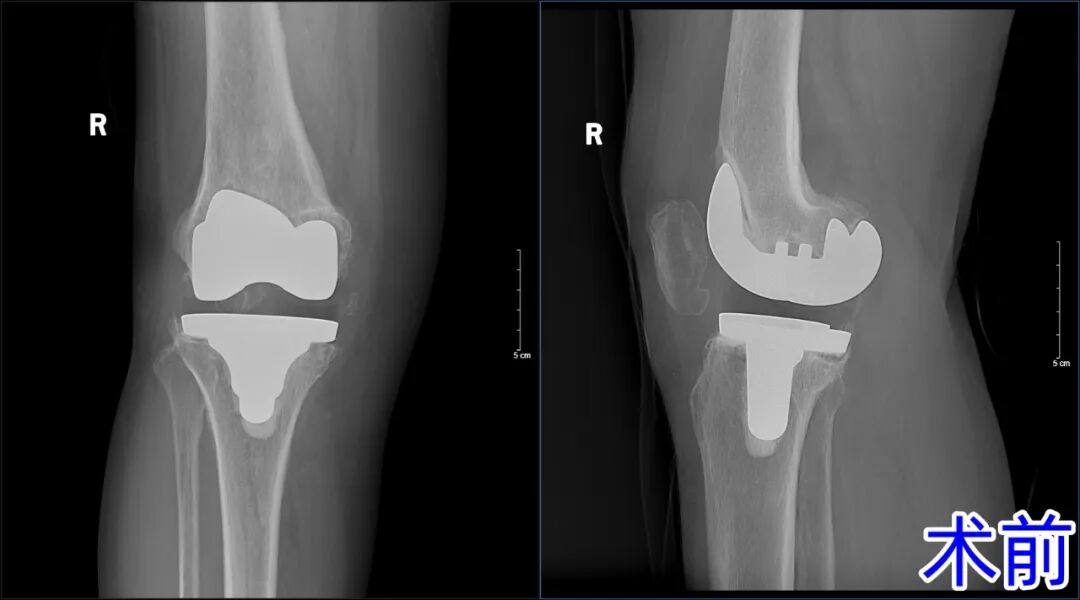

为进一步治疗,患者及家属慕名来到济南南郊医院。经过详细检查,杨学良主任发现患者右膝关节功能严重受限,基本上处于“直腿”状态,从影像学检查上看,假体周围存在松动迹象。经过科室讨论,患者有进行假体翻修的必要性,最终确定了“右膝关节翻修术”的手术方案。